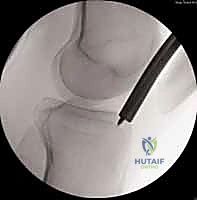

باستخدام جهاز الأشعة السينية المتحرك داخل غرفة العمليات (C-arm Fluoroscopy)، يتم سحب الساق وإعادتها لوضعها التشريحي الصحيح (Reduction) دون فتح منطقة الكسر.

بعد ذلك، يتم إدخال سلك دليلي معدني رفيع داخل القناة النخاعية، يليه استخدام أدوات توسيع دقيقة (Reamers) لتنظيف وتوسيع القناة وتجهيزها لاستقبال المسمار. هذه الخطوة بحد ذاتها تحفز نمو العظم من خلال نشر الخلايا العظمية داخل القناة.